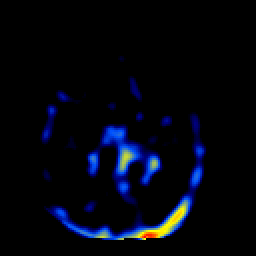

SPECT TL Study #2 -- Slice #30

[Home][Help][Clinical][Tour 1][Tour 2][Tour 3] Slice 30